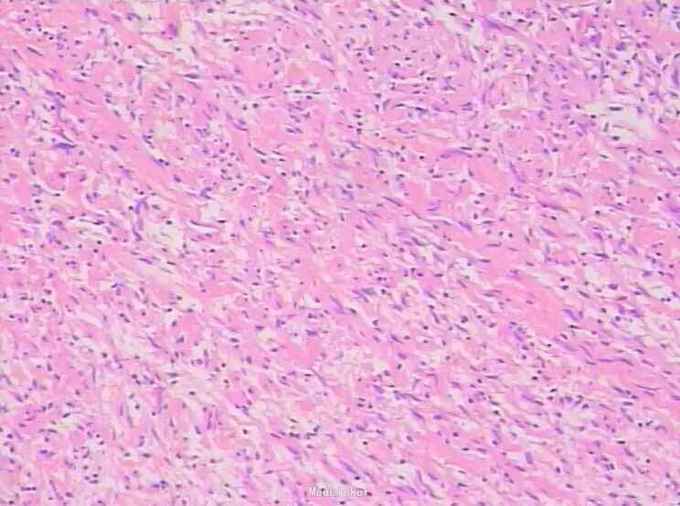

初步诊断:精囊肿瘤,性质不明。予手术切除治疗,术后病理:肉眼所见左侧精囊灰黄色包块,大小约4.5 cm×3.2 cm×2.6 cm,切面灰黄实性,质嫩。光镜下示瘤细胞核小,卵圆,无明显的细胞突起,为梭形细胞肿瘤;免疫组化:S-100(+),EMA(-),CK(-),VIM(+),CD34(部分+),CD117(-)。最后诊断:(原发性精囊)孤立性神经纤维瘤。